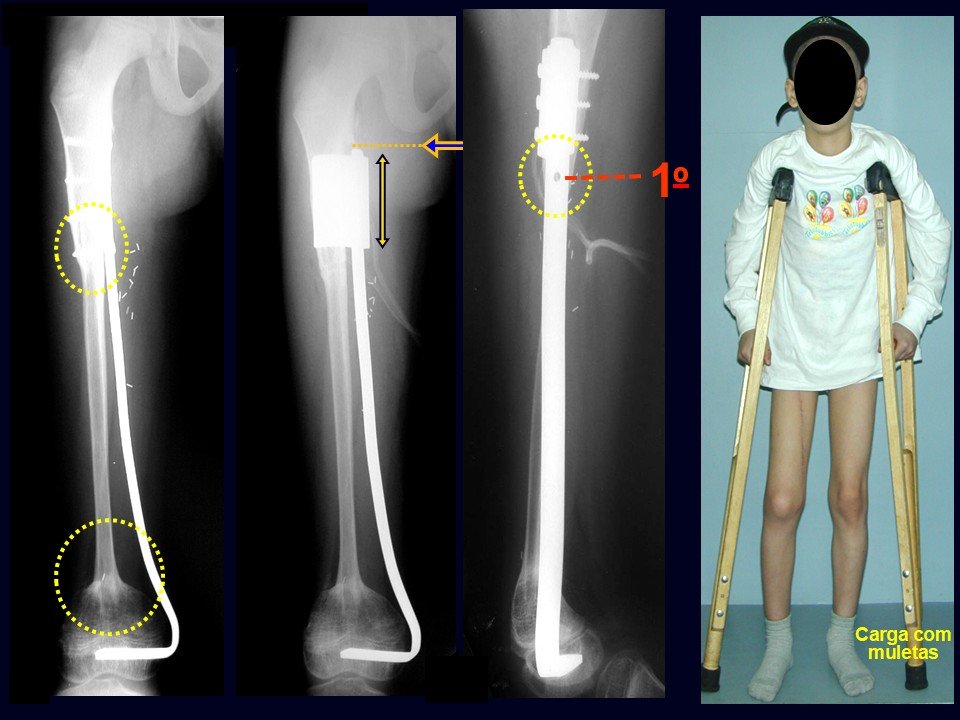

Vídeo 4: Este vídeo ilustra o deslizamento que os dispositivos de fixação interna extensível apresentam. A resolução deste caso permitiu a extrapolação dessa técnica para outras reconstruções em crianças em crescimento, possibilitando a encomenda de dispositivos feitos sob medida e adaptados para cada caso.